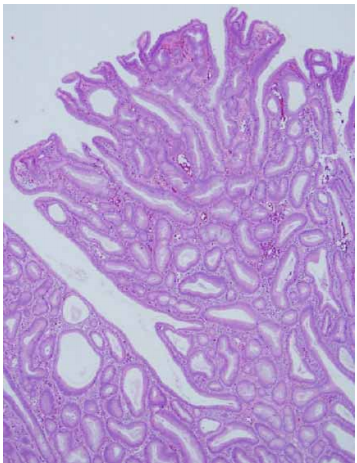

80 一位 65 歲女性於例行健康檢查發現右側乳房有一界線清楚結節,病理檢查如附圖,下列敘述何者正確?

(A)該腫瘤好發於年紀較大的女性,一般來說預後較其他種類的原發性乳房惡性腫瘤差 (B)一般來說都不會有激素接受器(hormone receptor)的表現 (C)該診斷為髓質癌(medullary carcinoma) (D)罹患該腫瘤的病人有 BRCA1 mutation 的機率較罹患其他種類的原發性乳房惡性腫瘤的病人要高